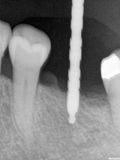

fredlibc | all galleries >> Galleries >> WYu - 36 impl > R1.jpg

R1.jpg